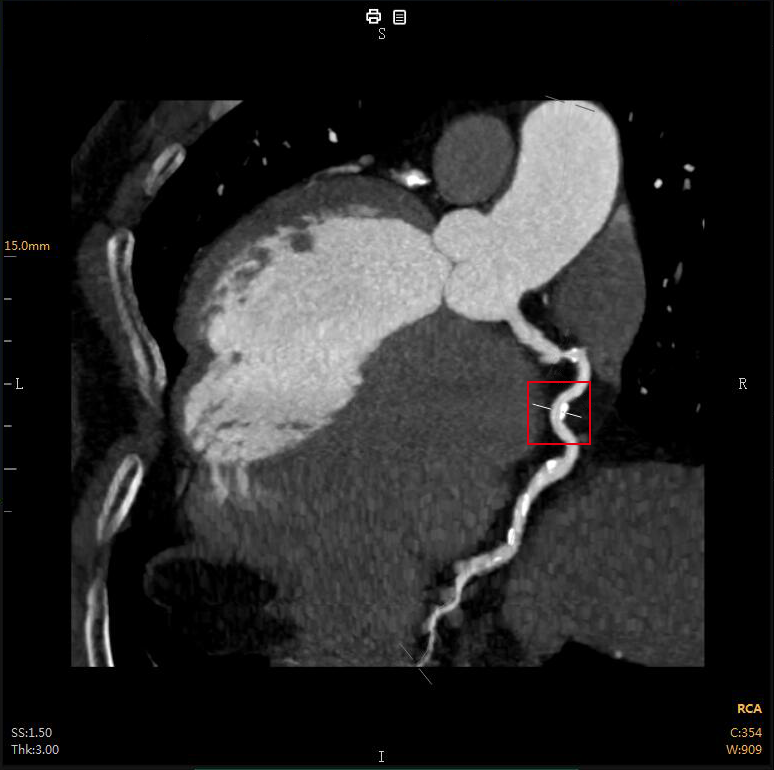

“CTA冠脉全自动诊断”

Automatic Coronary Diagnosis

CTA冠脉动脉造影以几乎无创的方式

成为冠心病的首选检查

①全自动图像重建/分割

②全自动量化测量

③全自动结构化报告

④全自动胶片及电子胶片输出

云端极速一气呵成

云端AI的CTA冠状动脉全自动诊断

重构了CTA冠脉检查的极简流程